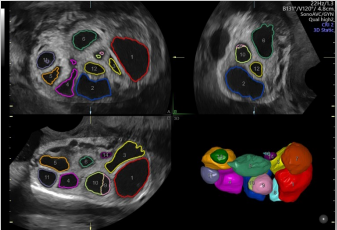

通過(guò)自動(dòng)的放置取樣框綠線并根據(jù)胎兒活動(dòng)自動(dòng)調(diào)節(jié),使得容積圖像的獲取更簡(jiǎn)單快速。